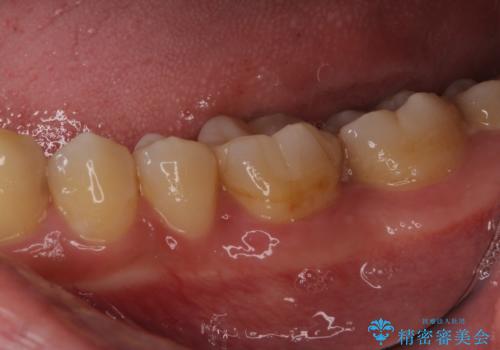

- 左下奥歯の銀歯のつめものがとれたことを主訴にご来院された患者様です。

1番奥の歯のセラミック治療をご希望されましたが、レントゲンなどの診査の結果、大きな虫歯などもありませんでした。

それよりも奥から2番目の歯のほうが、適合不良の銀のつめものが入っており、大きな虫歯が疑われました。

虫歯の大きさや形を加味して、1番奥を保険治療、奥から2番目をセラミック治療で行うことになりました。